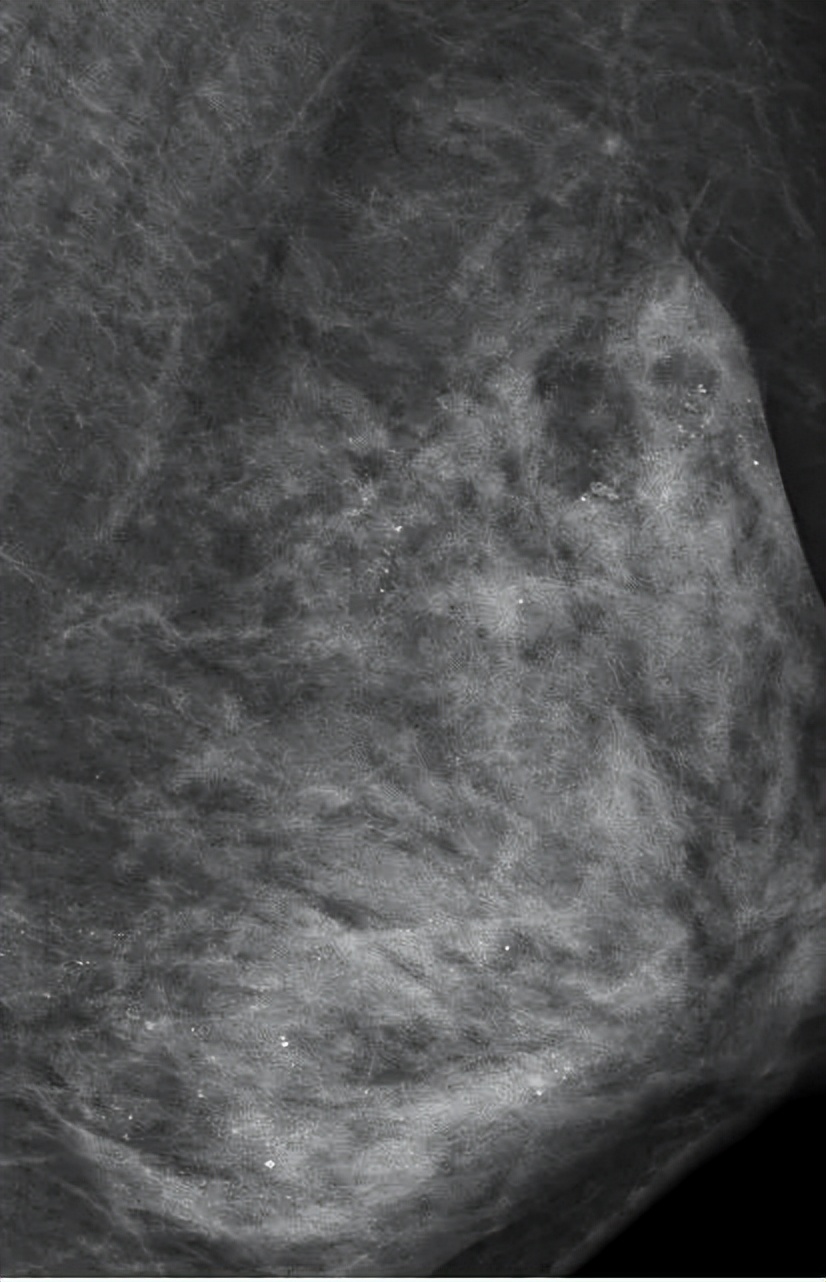

在一次体检中,做乳腺钼靶X线时,医生发现朱女士的左侧乳房布满众多细小如沙子一样、呈散在分布的钙化灶。

乳房布满白色钙化灶

乳房内出现钙化灶原因有很多,比如:可能是炎症或损伤渗出物留下的痕迹、新陈代谢后的钙盐沉积,也有可能是肿瘤造成的组织变化。

也就是说,钙化灶有可能是良性的病灶,也有可能是恶性的病灶。